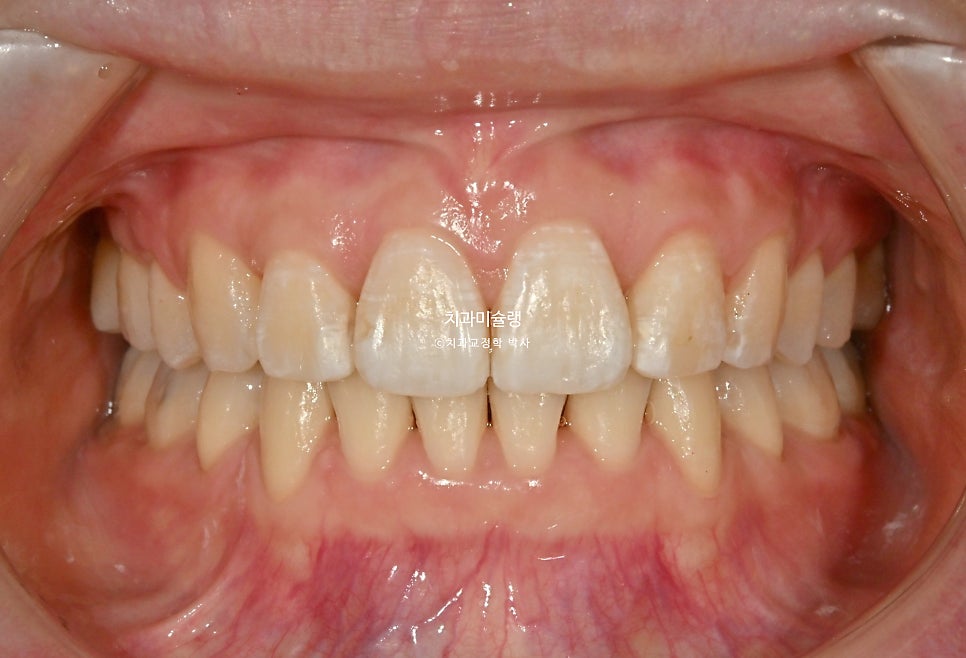

구강 내 변화 (2022.12-2026.02)

발치공간은 깔끔히 마무리 되었습니다.

환자분이 가장 고치고 싶어했던 앞니각도는 깔끔해졌습니다.

앞니 돌출로 인해 입이 편하게 안다물리던 입술부전증이 해소되어 위아래 입술이 편하게 다물리고

입술 사이로 빼꼼 보였던 앞니가 이제는 보이지 않습니다.

스마일라인은 아랫입술과 평행을 이루며

입술 돌출은 적당히 해소되었습니다.